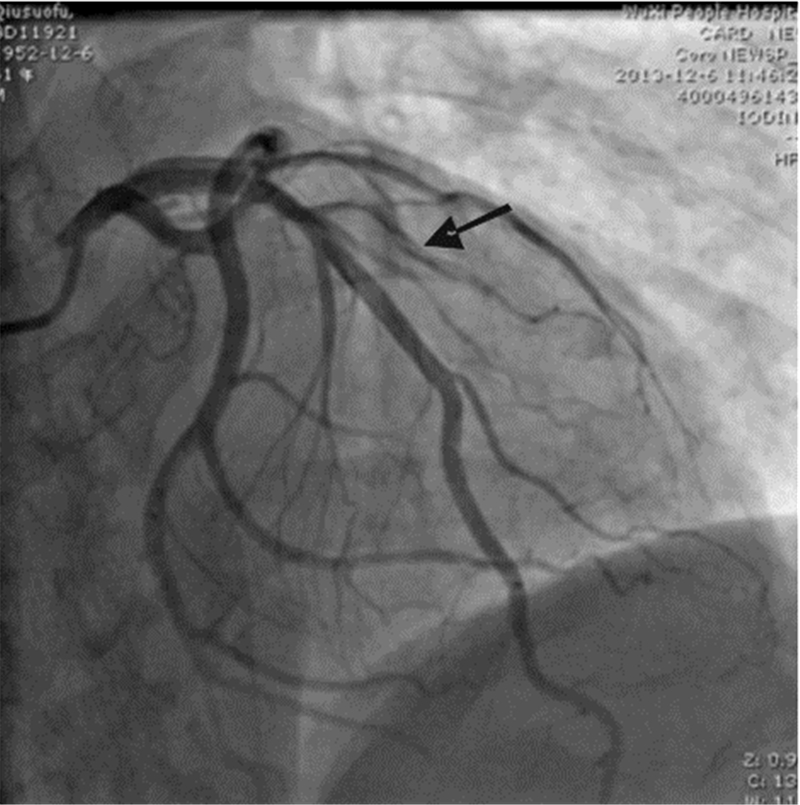

病例2 患者,男,61岁,因“发作性胸痛1 d”入院。 2013-11-29夜间打麻将时突发胸痛,位于胸骨中下段,伴有出冷汗,休息后胸痛持续不缓解,至当地医院急诊就诊,查心电图:窦性心动过缓,前壁导联T波高尖,当地医院予抗凝、抗血小板、扩冠等治疗后,症状持续约2 h缓解,复查心电图前壁导联T波较前稍低平,2013-11-30转来本院。否认高血压病及糖尿病史,有吸烟史30年,平均20支/ d。入院查体:BP 111/63 mmHg,神清,呼吸平,两肺呼吸音粗,两肺未及啰音,心率71次/min,律齐,未及病理性杂音,腹软,无压痛,双下肢无浮肿。心肌酶谱:CK-MB 90 U/L,CK 853 U/L,AST 131 U/L,LDH 761 U/L。入院时心电图:avL病理性Q波形成,T波倒置(图 3)。诊断:急性非ST段抬高性心肌梗死,冠状动脉粥样硬化性心脏病,心功能Killip Ⅰ级。入院后查心电图未见明显动态演变,心肌酶谱符合急性心肌梗死的动态演变,肌钙蛋白I阳性,床边心超未见明显异常,2013-12-06行冠脉造影显示第二对角支中段自发性夹层形成,造影剂滞留(图 4),由于第二对角支血管较细,未行支架植入,出院后药物治疗至今,患者无不适。

| 图 4 病例2冠脉造影结果(箭头示D2自发性夹层) |